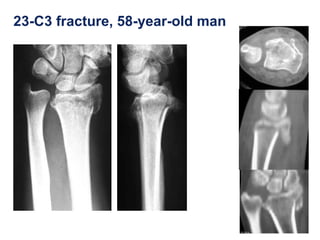

23-C3 fracture, 58-year-old man

โ€ข Even in a severely multifragmentary fracture stabilty is

satisfactory with the distal radius plate

1 year and 4 months postoperatively